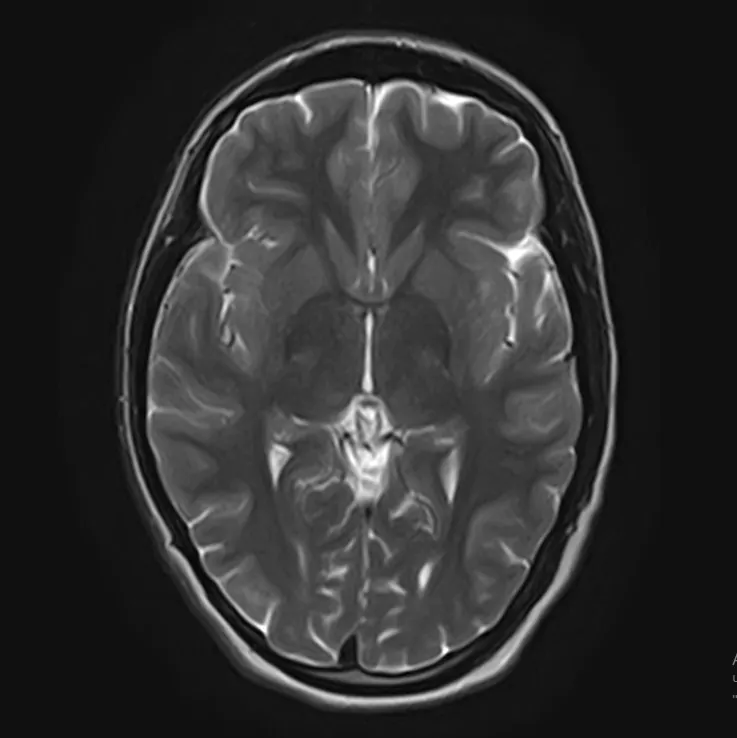

3️⃣ При головной боли, надо обязательно сделать МРТ

Действительно, зачастую приходят на МРТ пациенты, страдающие головной болью. Однако, в подавляющих случаях, МРТ не дает каких-то неблагоприятных результатов. Такая головная боль, как правило, связана с психоэмоциональными или психофизиологическими особенностями как организма, так и образа жизни (стресс, переутомление, несоблюдение режима труда и отдыха и т.д.). Но стоит отметить, что проведение МРТ даст дополнительную информацию Вам о состояние головного мозга  и тем самым “успокоит” Вас.